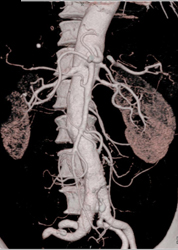

Clot in Superficial Femoral Artery (SFA) Due to Trauma in A Child-MIP Vs VRT